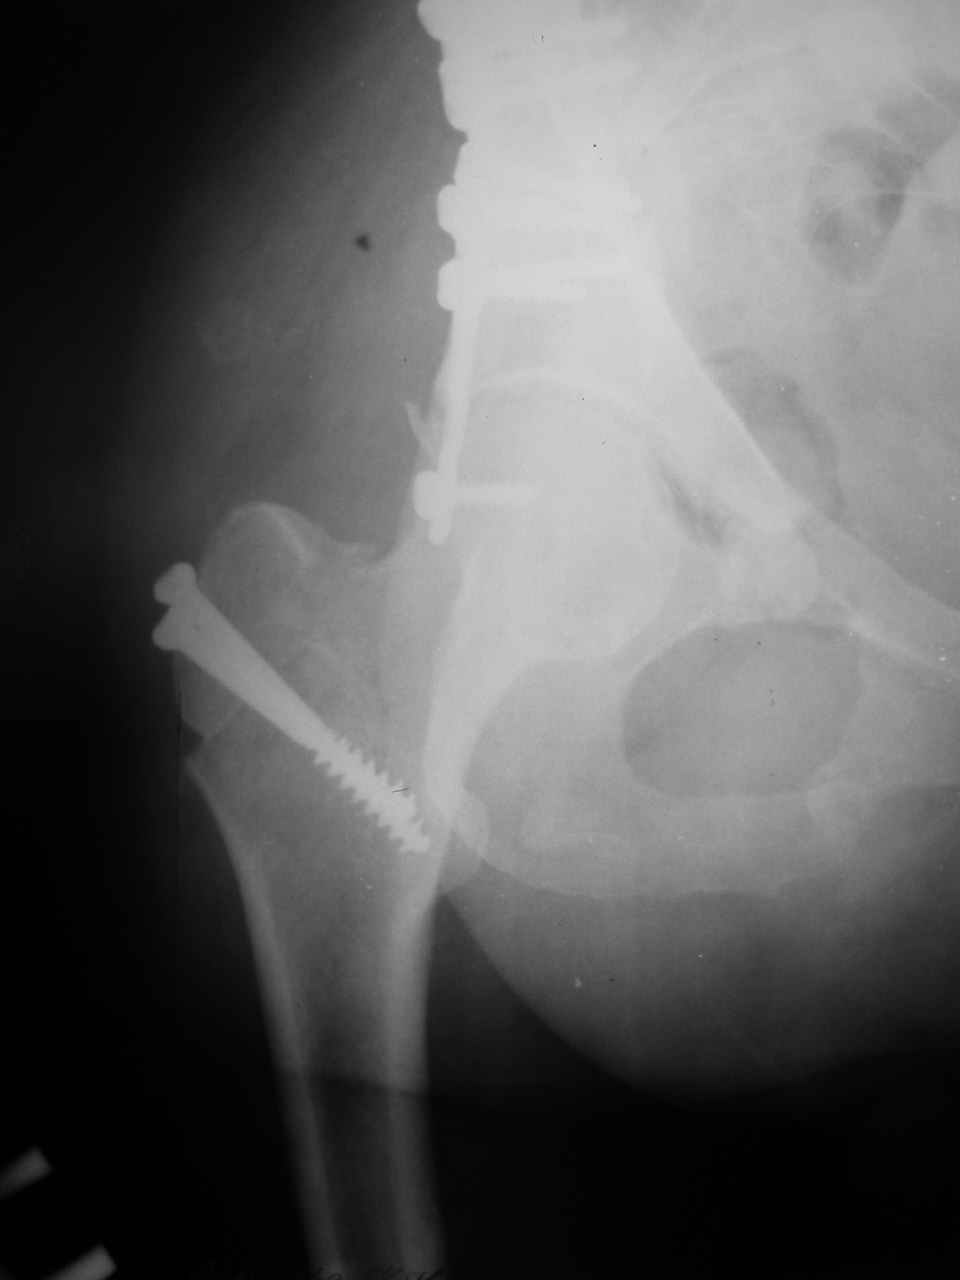

Снимки и схема